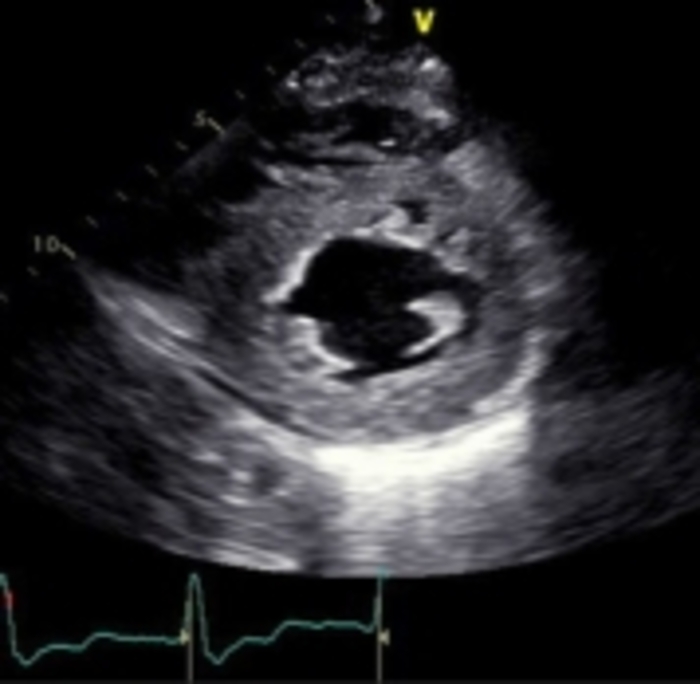

1. Echo imaging that reveals LV hypertrophy may be indicative of cardiac amyloidosis (CA)

2. GLS pattern of apical sparing is associated with CA